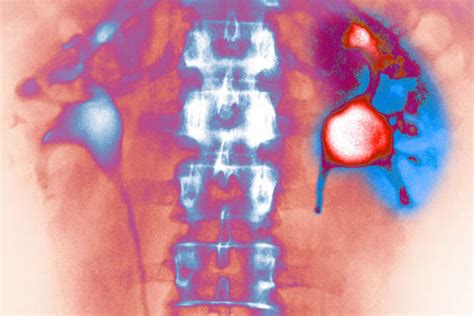

Let’s rewind a bit and talk about the absolute superstars of our internal filtering system: our kidneys. Seriously, guys, these organs are working 24 7 to keep us alive and well, and a massive part of that job is waste removal and filtration . Imagine your blood as a river carrying all sorts of things – nutrients, oxygen, hormones, but also metabolic byproducts, toxins, and excess salts. Your kidneys are the sophisticated water treatment plants that process this river. The kidney’s role in waste removal and filtration is nothing short of miraculous. Every single minute, your kidneys filter about a quarter of your total blood volume – that’s a lot of processing power! This filtering happens in tiny units called nephrons, and within each nephron, there’s a complex structure called the glomerulus. The glomerulus acts like a sieve, allowing small molecules like water, salts, glucose, and waste products (like urea) to pass through into the renal tubules, while keeping larger things like blood cells and big proteins in the bloodstream. As the filtered fluid travels through the tubules, the magic of selective reabsorption and secretion happens. Your body smartly reabsorbs the good stuff – like most of the water, essential salts, and glucose – back into the blood. At the same time, it actively secretes any remaining waste products and excess ions into the fluid. What’s left is urine, which then travels down to your bladder to be expelled from the body. This entire process is incredibly precise, ensuring that you get rid of harmful waste without losing essential nutrients or fluids. Now, think about what could go wrong. If the filtration barrier in the glomerulus gets damaged, larger molecules like proteins can leak into the urine (a sign of kidney disease). If the tubules can’t reabsorb water properly, you can become dehydrated. If waste products aren’t filtered out effectively, they build up in the blood, leading to toxic levels. This is where understanding the potential PSEglpse-1 effects on kidneys comes into play. If PSEglpse-1 is involved in maintaining the integrity of that glomerular filter, or in regulating the transport of substances across the tubular membranes, then any imbalance or dysfunction related to PSEglpse-1 could directly impair the kidney’s ability to perform these vital filtration and waste removal tasks. It highlights just how interconnected everything is within our bodies and why even a seemingly small protein could have significant repercussions on such a critical organ system. It’s truly mind-blowing!